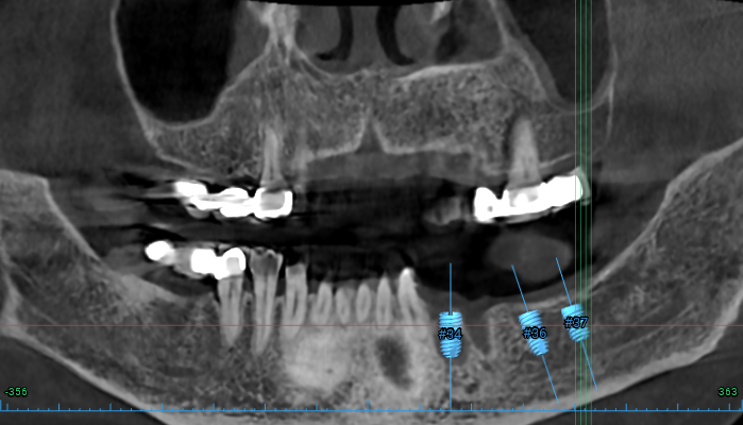

#34,36,37 자리에 임플란트를 식립할 예정이었어요.

#34번 부위는 임플란트를 위치시키고 나면 협측으로 뼈이식을 반드시 넉넉하게 해야할 모양새였습니다.

비교적 뽑은지 오래되었던 #36,37 치아는 잇몸뼈가 넉넉하게 보였습니다.

두 큰어금니 부위는 하치조신경관(아래이틀신경)만 조심해서 적절한 임플란트를 심어놓으면 되었습니다.